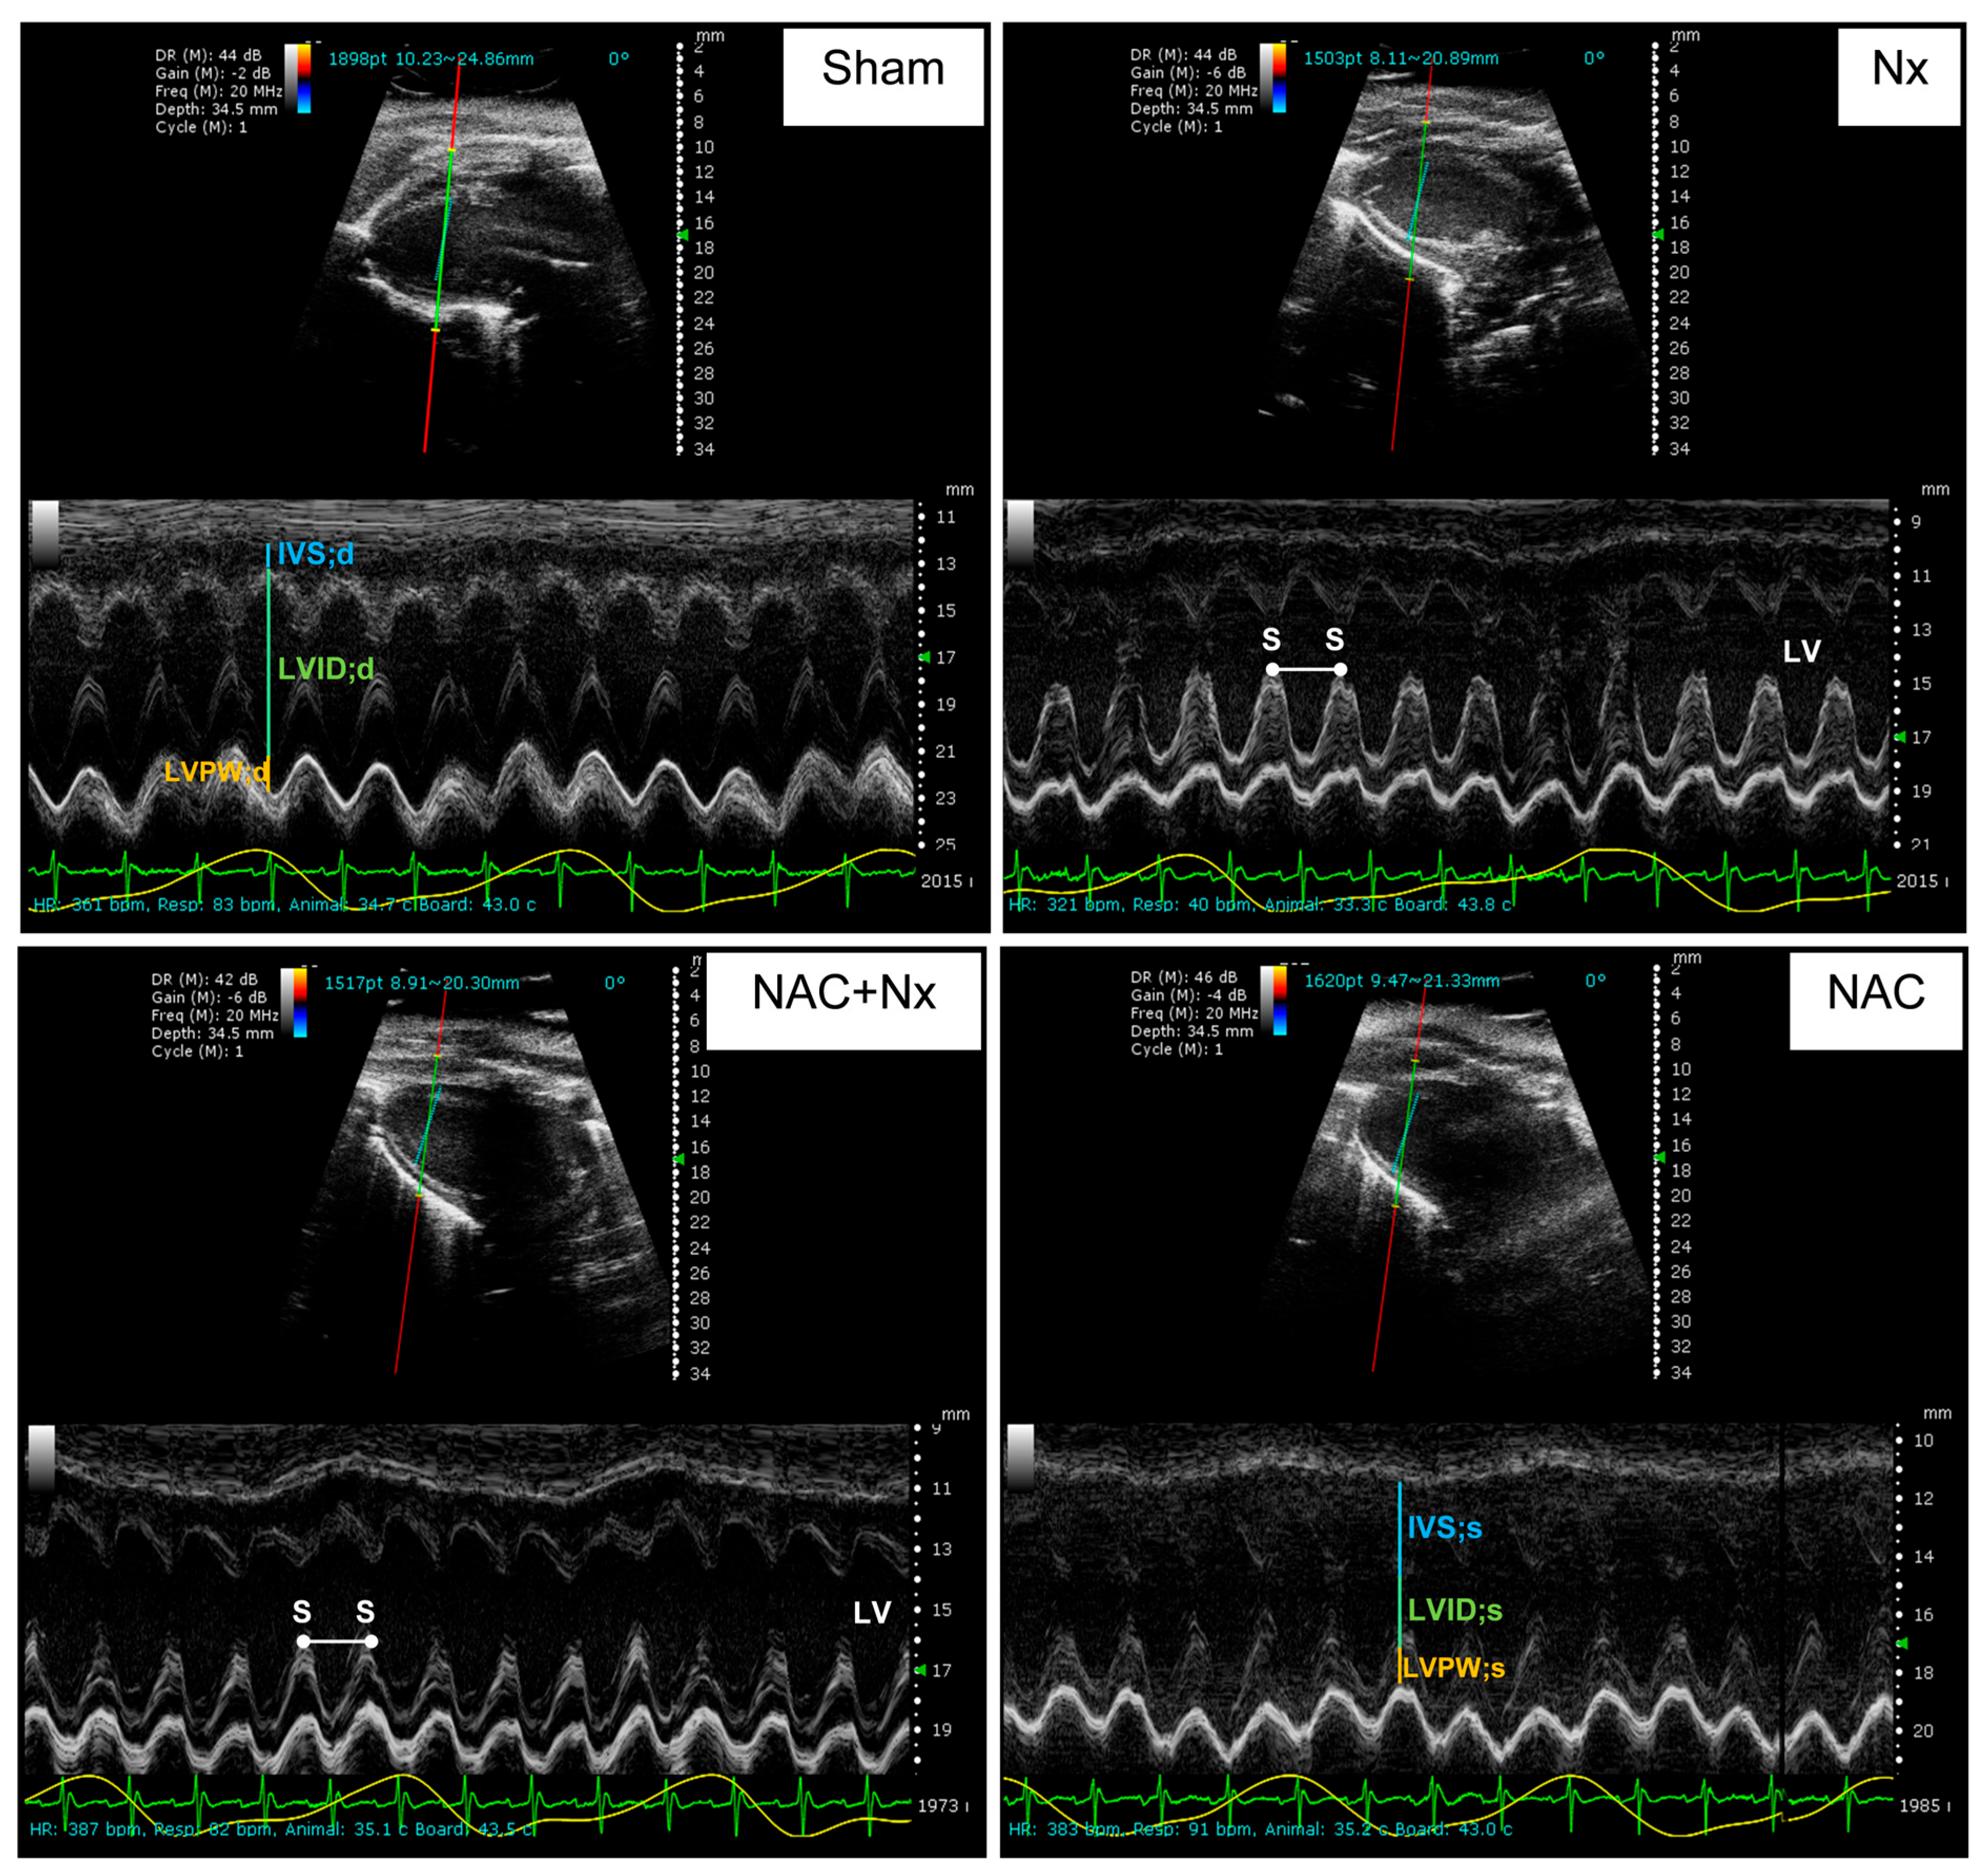

| Parameter | Sham | NX | NAC+NX | NAC |

|---|---|---|---|---|

| HR (bpm) | 355.9 ± 19.3 | 365.2 ± 23.5 | 391 ± 24.6 | 365.9 ± 28.9 |

| IVS;d (mm) | 0.9 ± 0.1 | 1.1 ± 0.2 | 1.1 ± 0.3 | 1.1 ± 0.3 |

| LVID;d (mm) | 6.9 ± 0.8 | 6.7 ± 0.7 | 6 ± 0.6 | 6.8 ± 0.7 |

| LVPW;d (mm) | 1.5 ± 0.3 | 1.2 ± 0.2 | 1.3 ± 0.3 | 1.2 ± 0.1 |

| FS (%) | 57.8 ± 14.2 | 38.5 ± 7.9 * | 52 ± 9.9 *** | 52.1 ± 5.5 |

| EDV (µL) | 253.5 ± 65.9 | 236.2 ± 52.4 | 181.7 ± 39.9 | 245.6 ± 52.9 |

| ESV (µL) | 42.4 ± 37.1 | 78.2 ± 28.3 | 35.3 ± 17.5 *** | 48.3 ± 18.8 |

| EF (%) | 84.3 ± 10.1 | 66.5 ± 9.5 *,** | 80.1 ± 9.6 *** | 81.1 ± 4.6 |

| SV (µL) | 211.1 ± 42.9 | 158 ± 44.1 | 146.4 ± 36.2 * | 197.3 ± 36 |

| CO (mL/min) | 76.7 ± 17.7 | 57.2 ± 15.4 | 57.5 ± 15.1 | 72 ± 14 |